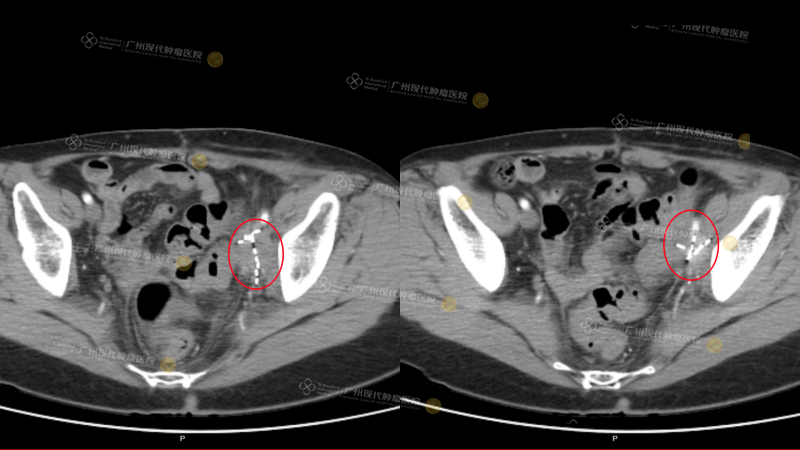

ผลการรักษาปรากฏชัดอย่างรวดเร็ว—หลังการรักษาครั้งแรกเสร็จสิ้นอาการปวดท้องที่ทรมานเธอมานานก็หายไปหลังการรักษาครั้งที่สองการไหลเวียนเลือดที่ขากลับมาดีขึ้นอาการบวมของขาซ้ายลดลงอย่างเห็นได้ชัด“สิ่งนี้ทำให้ฉันมีความมั่นใจอย่างมาก” ฟู อ้ายฉินเล่าด้วยความตื่นเต้น“หลังจบการรักษาครั้งที่สี่ ได้ทำการตรวจ PET Scanก็เห็นได้ชัดจริงๆว่าก้อนมะเร็งหดเล็กลงอย่างมาก”ตลอดระยะเวลาการรักษา 3 เดือน จนถึงปัจจุบันต่อมน้ำเหลืองในอุ้งเชิงกรานของฟู อ้ายฉินแทบจะไม่มีกิจกรรมของโรคเหลืออยู่แล้ว ก้อนมะเร็งที่ตับ หายไปโดยไม่พบรอยโรคการประเมินผลการรักษาโดยรวมสามารถจัดอยู่ในระดับ PR

(อุ้งเชิงกราน: หลังการรักษา 2 ครั้ง ก้อนมะเร็งหดเล็กลง 80%) (บริเวณสีขาวที่ไฮไลต์ คือเมล็ดแร่ที่ทำการฝัง)